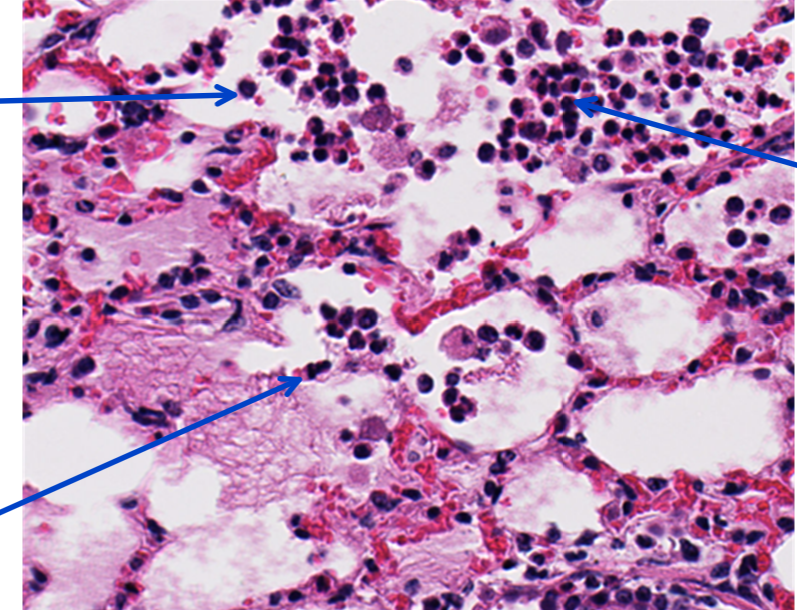

This is a slide from a bovine lung.What would the cellular exudate be composed of in this lesion?

macrophages, neutrophils, and necrotic alveolar epithelium

Identify this structure:

neutrophils

fibrin

Q

interlobular lymphatics with fibrin and hemorrhage

10

fibrin thrombi

12